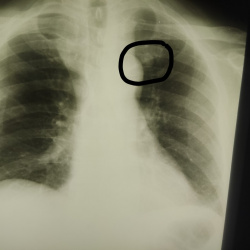

Здравствуйте. Молодой пациент, пришёл на комиссию. На уровне переднего отдела 1 ребра справа тень расценила как обызвествление в хрящевом отделе. Хотелось бы услышать ваши мнения, а то может быть зря...